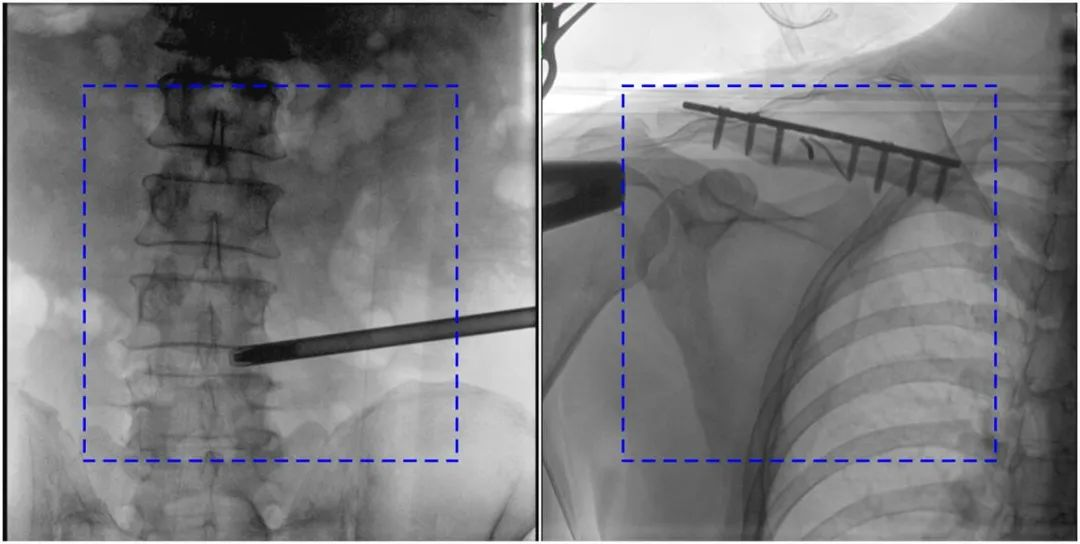

与传统的21CM×21CM成像尺寸相比,糖心vlog 大平板一体式C形臂具有30CM×30CM更大成像尺寸,能够一次成像5.5节椎体,呈现更全面的影像信息,即便是手术经验不丰富的年轻医生也能通过图像迅速判断椎体节段、定位手术部位,避免因为视野不足而造成的多次定位、反复曝光,提高效率的同时避免过量摄入辐射。

糖心vlog 大平板一体式C形臂图像与传统图像对比(蓝色虚线内为传统21CM×21CM平板的成像区域)